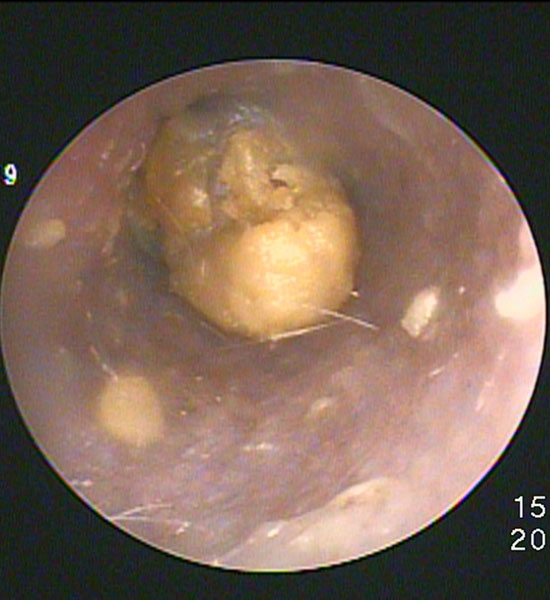

耳内にポリープが増殖しています。

適切な管理ができないと徐々にポリープが大きくなり耳道を塞ぎます。

犬種としては「A・コッカー」「シーズー」などでよくみられます。

内視鏡下で半導体レーザーにて蒸散することで耳道を広げることができます。